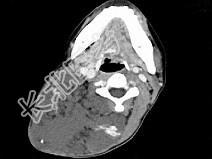

- 单项选择题女,32岁, 颈部包块8年余,包块逐渐长大, CT如图所示,最可能的诊断为 ( )

A、颈部神经纤维瘤

B、颈部横纹肌肉瘤

C、颈部巨大血管瘤

D、颈部神经鞘瘤

E、颈部异位甲状腺